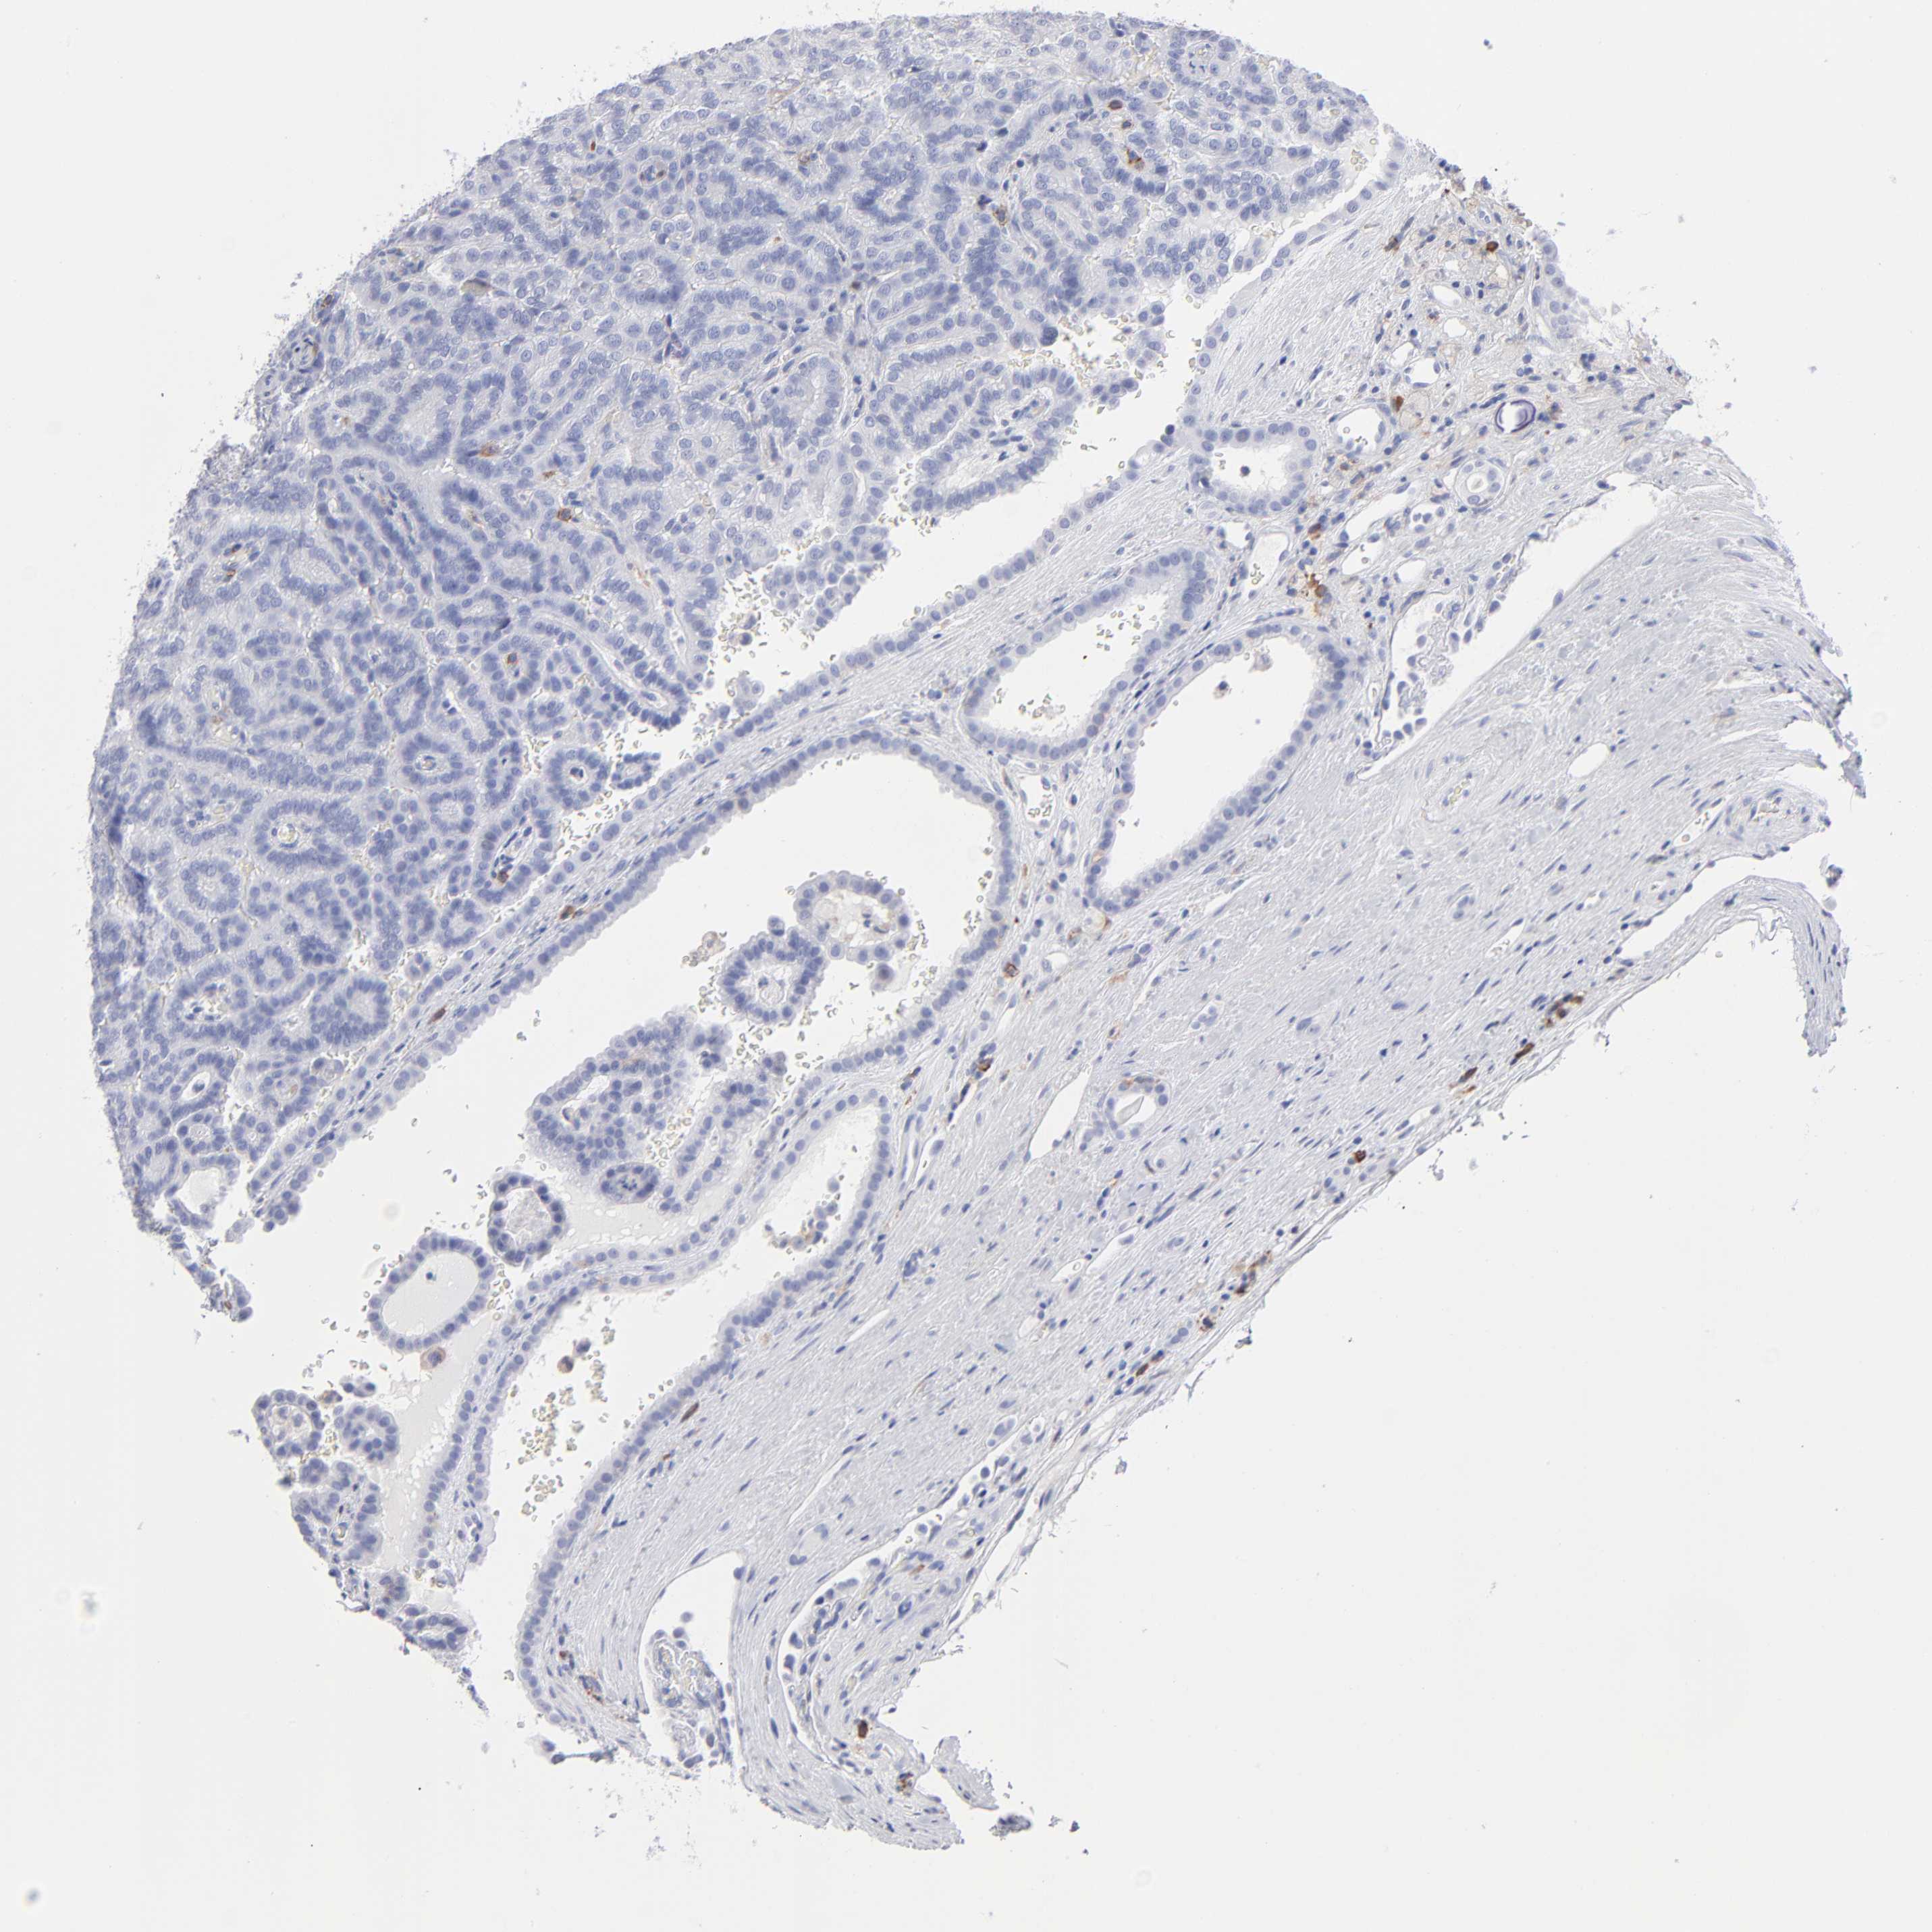

Renal cancer

Kidney renal clear cell carcinoma